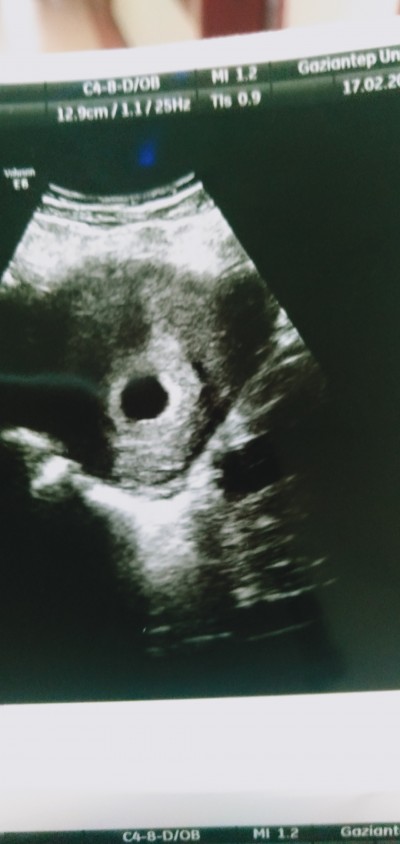

Cinsiyet tahmini yapar mısınız

Gebelik haftası 10 hafta

2 foto attım görünmüyor galiba bebek gorunuyor ama bazı kişiler kese fotoğrafindan tahmin ediyormuş merak ettim anlayan varmı diye

Kese fotorafindan kiza benzettim ama yine de tahmin